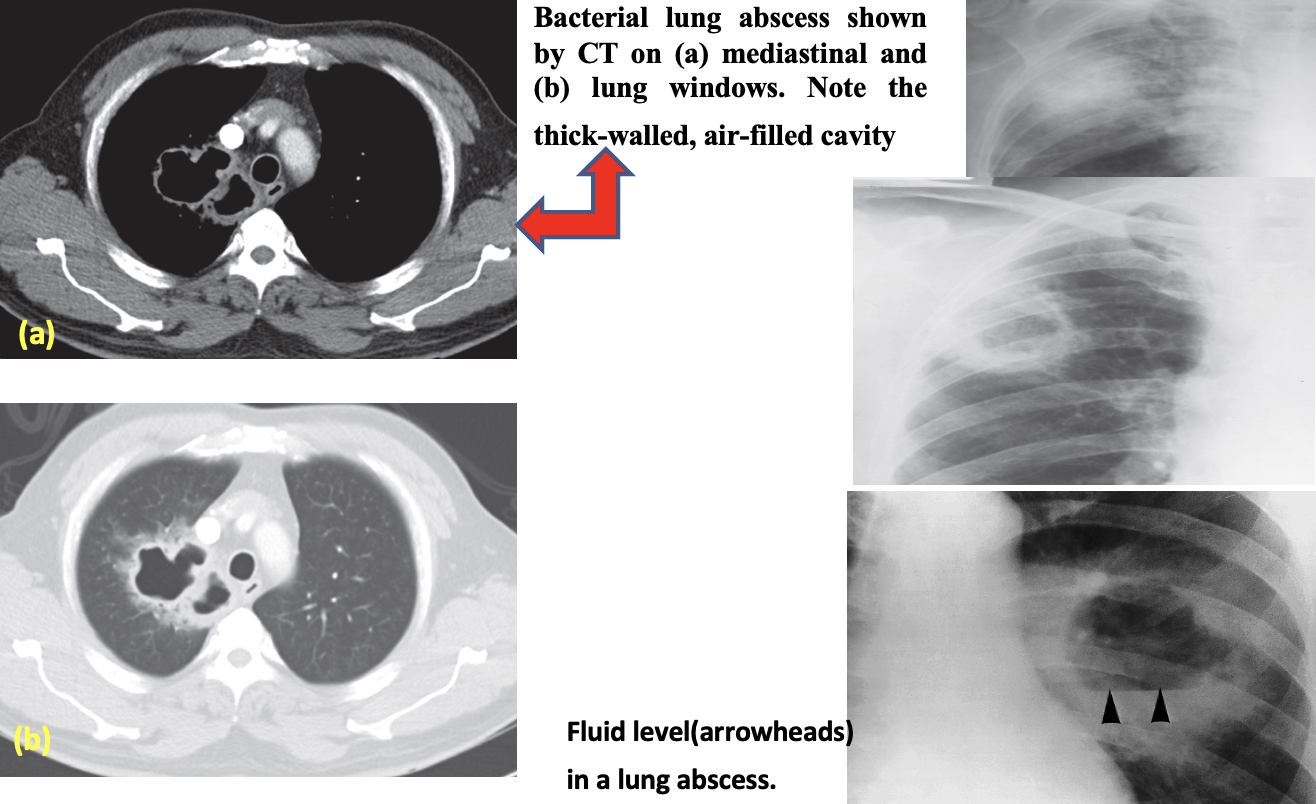

The diagnosis is suggested by a chest radiograph demonstrating a thick-walled cavity with an air-fluid level and confirmed by contrast-enhanced computed tomography .

Anterior view of a chest radiograph in a patient with thick-walled right lung abscess. The patient later developed a brain abscess.

Air fluid level

Cavitation (abscess formation):

The air is then seen as a transradiancy within the consolidation and an air–fluid level may be present

CT is better and more sensitive than CXR for demonstrating cavitation